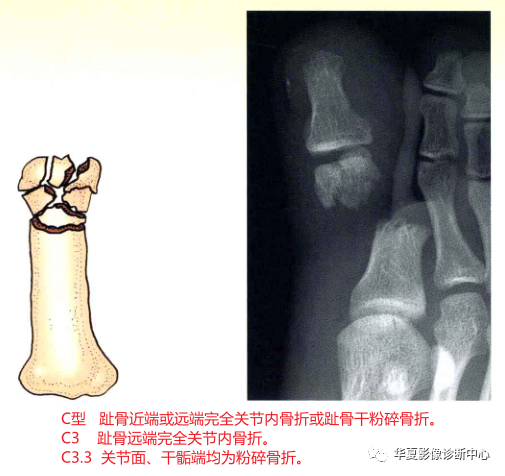

C型趾骨近端或远端完全关节内骨折或趾骨干粉碎骨折。

C3:趾骨远端完全关节内骨折。又分为:

C3.1:关节面、干骺端均为简单骨折;

C3.2:关节面简单、干骺端粉碎骨折;

C3.3:关节面、干骺端均为粉碎骨折。